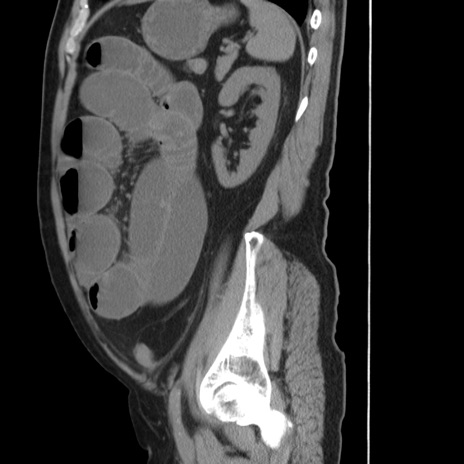

症例20(矢状断像)

【症例】 60歳代男性

【主訴】 腹部膨満、嘔吐

【現病歴】5日前頃より倦怠感を認め食事量減少し4日前の朝嘔吐、食事摂取困難となった。 3日前近医受診し点滴施行され整腸剤などを処方された。 当日他院を受診し、腹部膨満著明、炎症反応の上昇(CRP10.8、WBC11200)あり、紹介受診となる。

【身体所見】 意識JCS1 受け答えがはっきりしないBP 111/57mHg、 P 67bpm、、BT35.2°C、SpO2 97%(RA)、 腹部:膨隆、打診で鼓音あり、全体的に圧痛有り、腸蠕動音(-)、反跳痛ははっきりせず。

【データ】WBC 11400、CRP 14.20